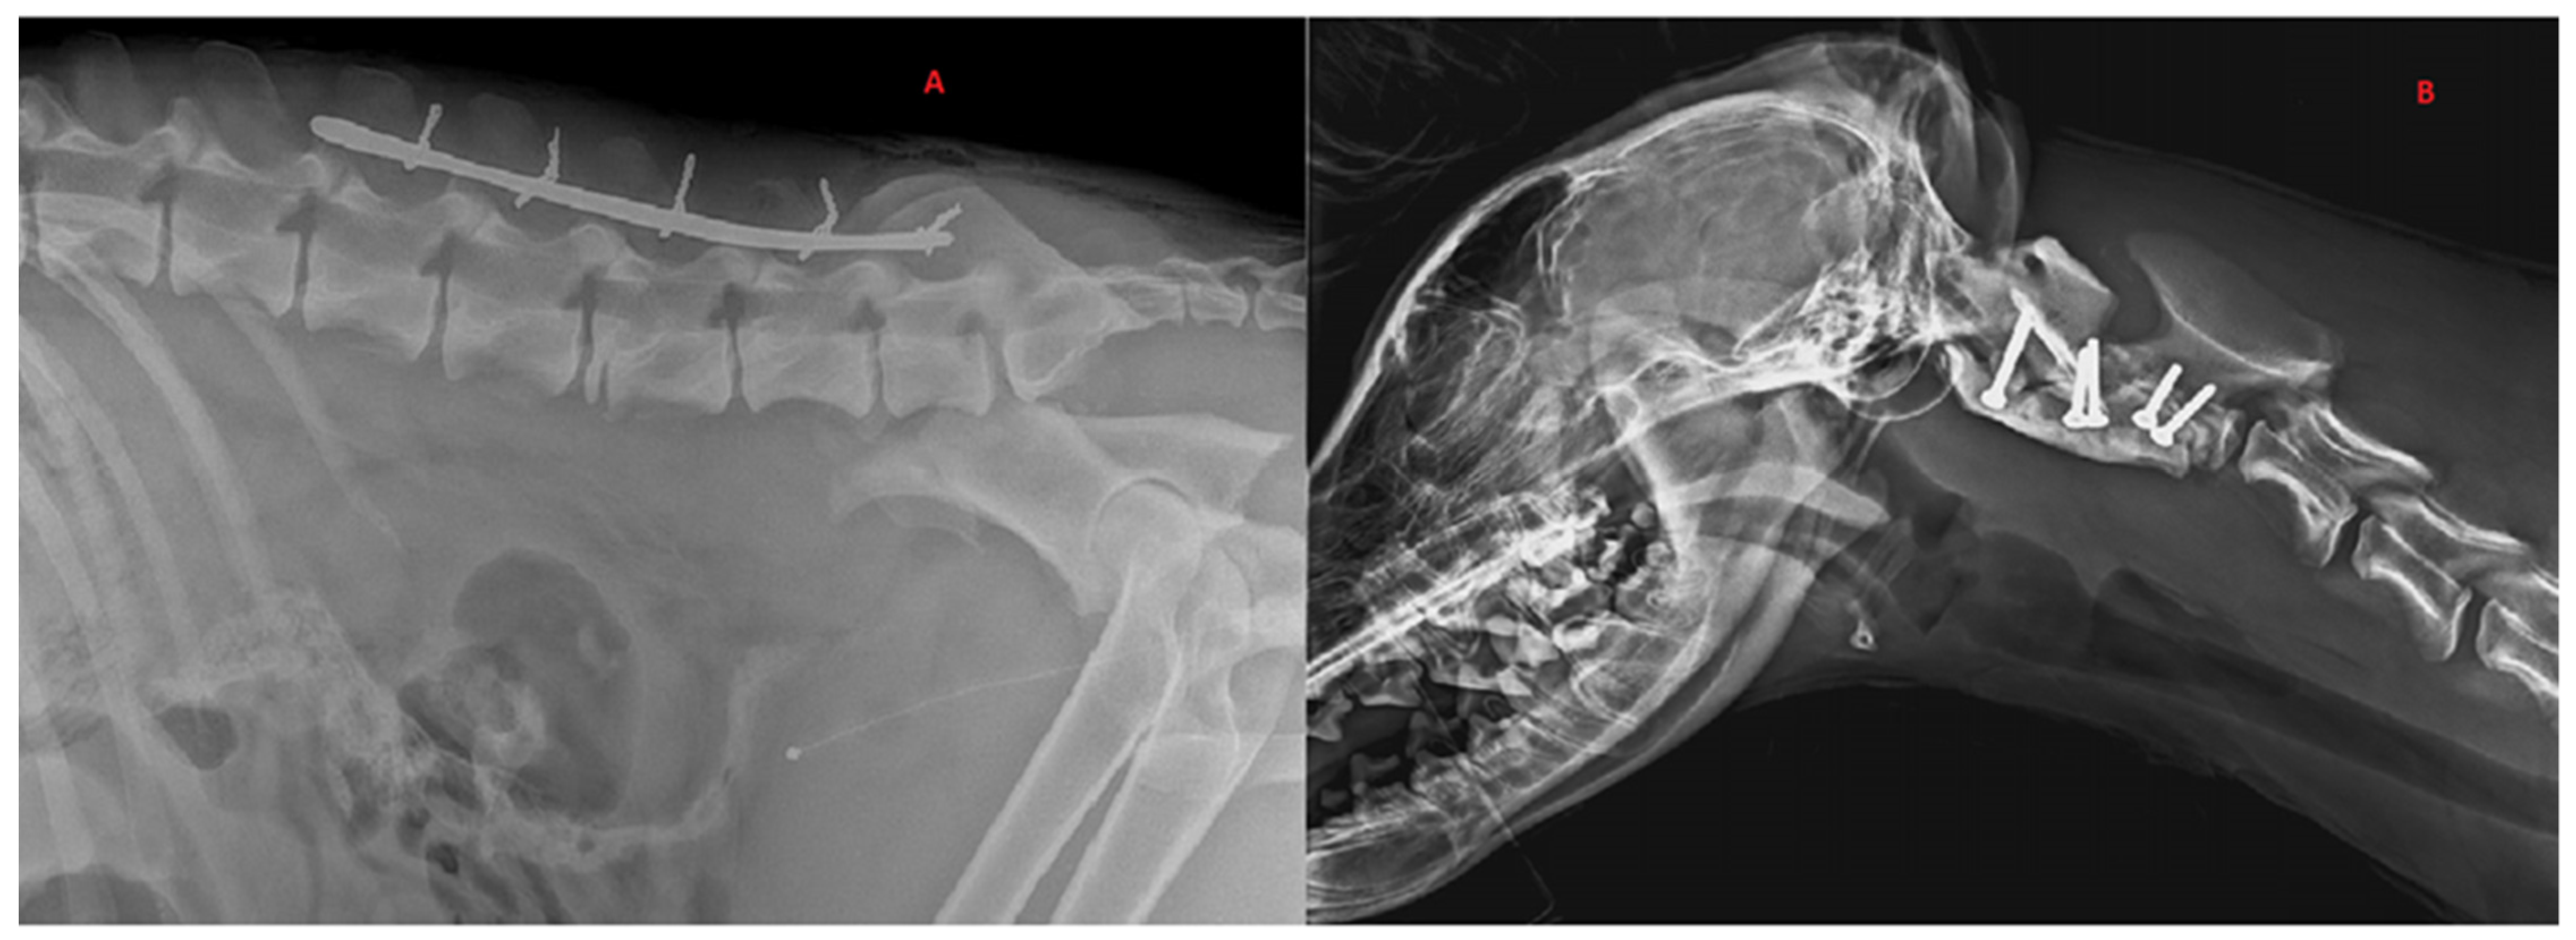

Figure 3.

Radiographic exams. (A) Application of dorsal spinal staple in 50-month-old, male, Italian wolf with L5 vertebral fracture. Bilateral ileal: body oblique fractures; (B) application of ventral implant with screw–PMMA in 7-month-old, female, Italian wolf with C2 vertebral fracture and luxation.